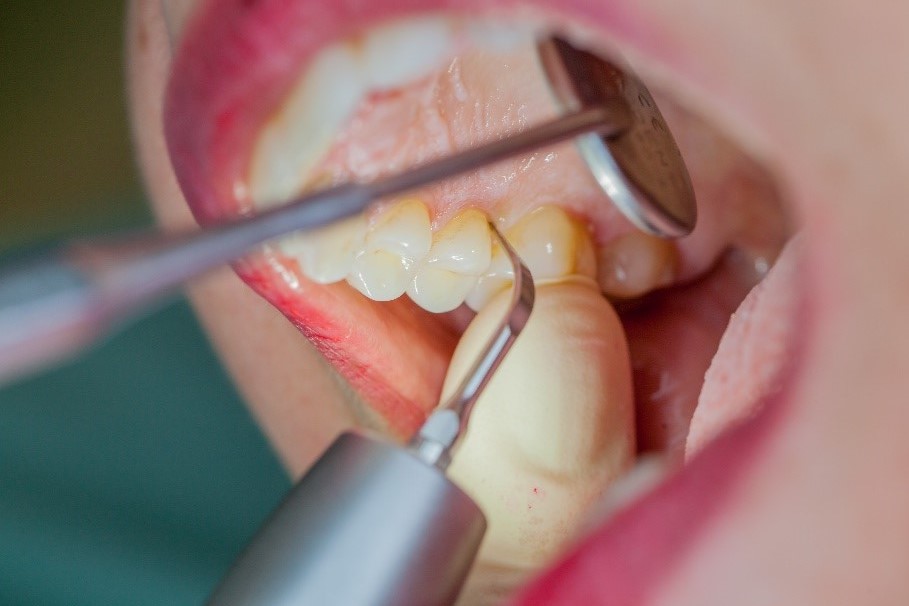

Dans le cadre du traitement parodontal préventif, le détartrage subgingival (debridement en anglais) est effectué à l'aide d'appareils à ultrasons et d'inserts paro spécifiques (Fig. 3). Des instruments manuels peuvent également être utilisés. En fonction de la situation, d'autres mesures, y compris chirurgicales et régénératives, peuvent s’avérer nécessaires.